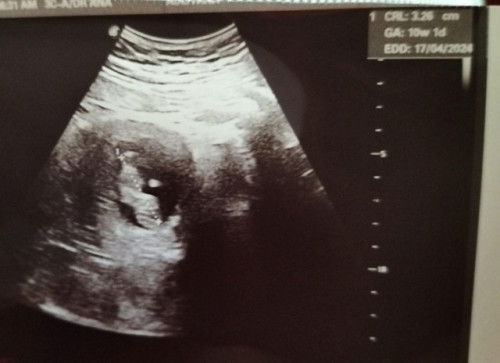

ALHAMDULILLAH BABY MEMBESAR DENGAN SIHAT

Alhamdulillah w semalam g klinik swasta semata2 nak g scan baby (2nd appt di KK 3/10 lambat lagi 😆), first to be mom setelah 7tahun menanti mmg excited sgt2. Syukur scan baby dah pusing2 golek2 dlm perut mummy, besar mengikut tarikhnya, dengar heartbeat so cute. Semoga Allah jaga kandungan ini dan membesar dgn sempurna ye anakku. So excited ... alhamdulillah Syukur 🤲 #firstmom #firstbaby

Got a bun in the oven